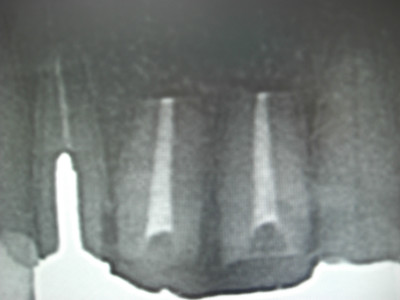

今日のオペは上顎左右1番の歯根端切除と骨補填です。

この部位の根尖には歯冠大の歯根嚢胞があり、ずっと根管治療を行ってきたのですが、根尖からの排膿が消失せずなかなか良くならなかった為に、歯根嚢胞と感染した根尖部を根こそぎ除去してしまう歯根端切除術,及び骨補填する術式を選択することになった次第です。